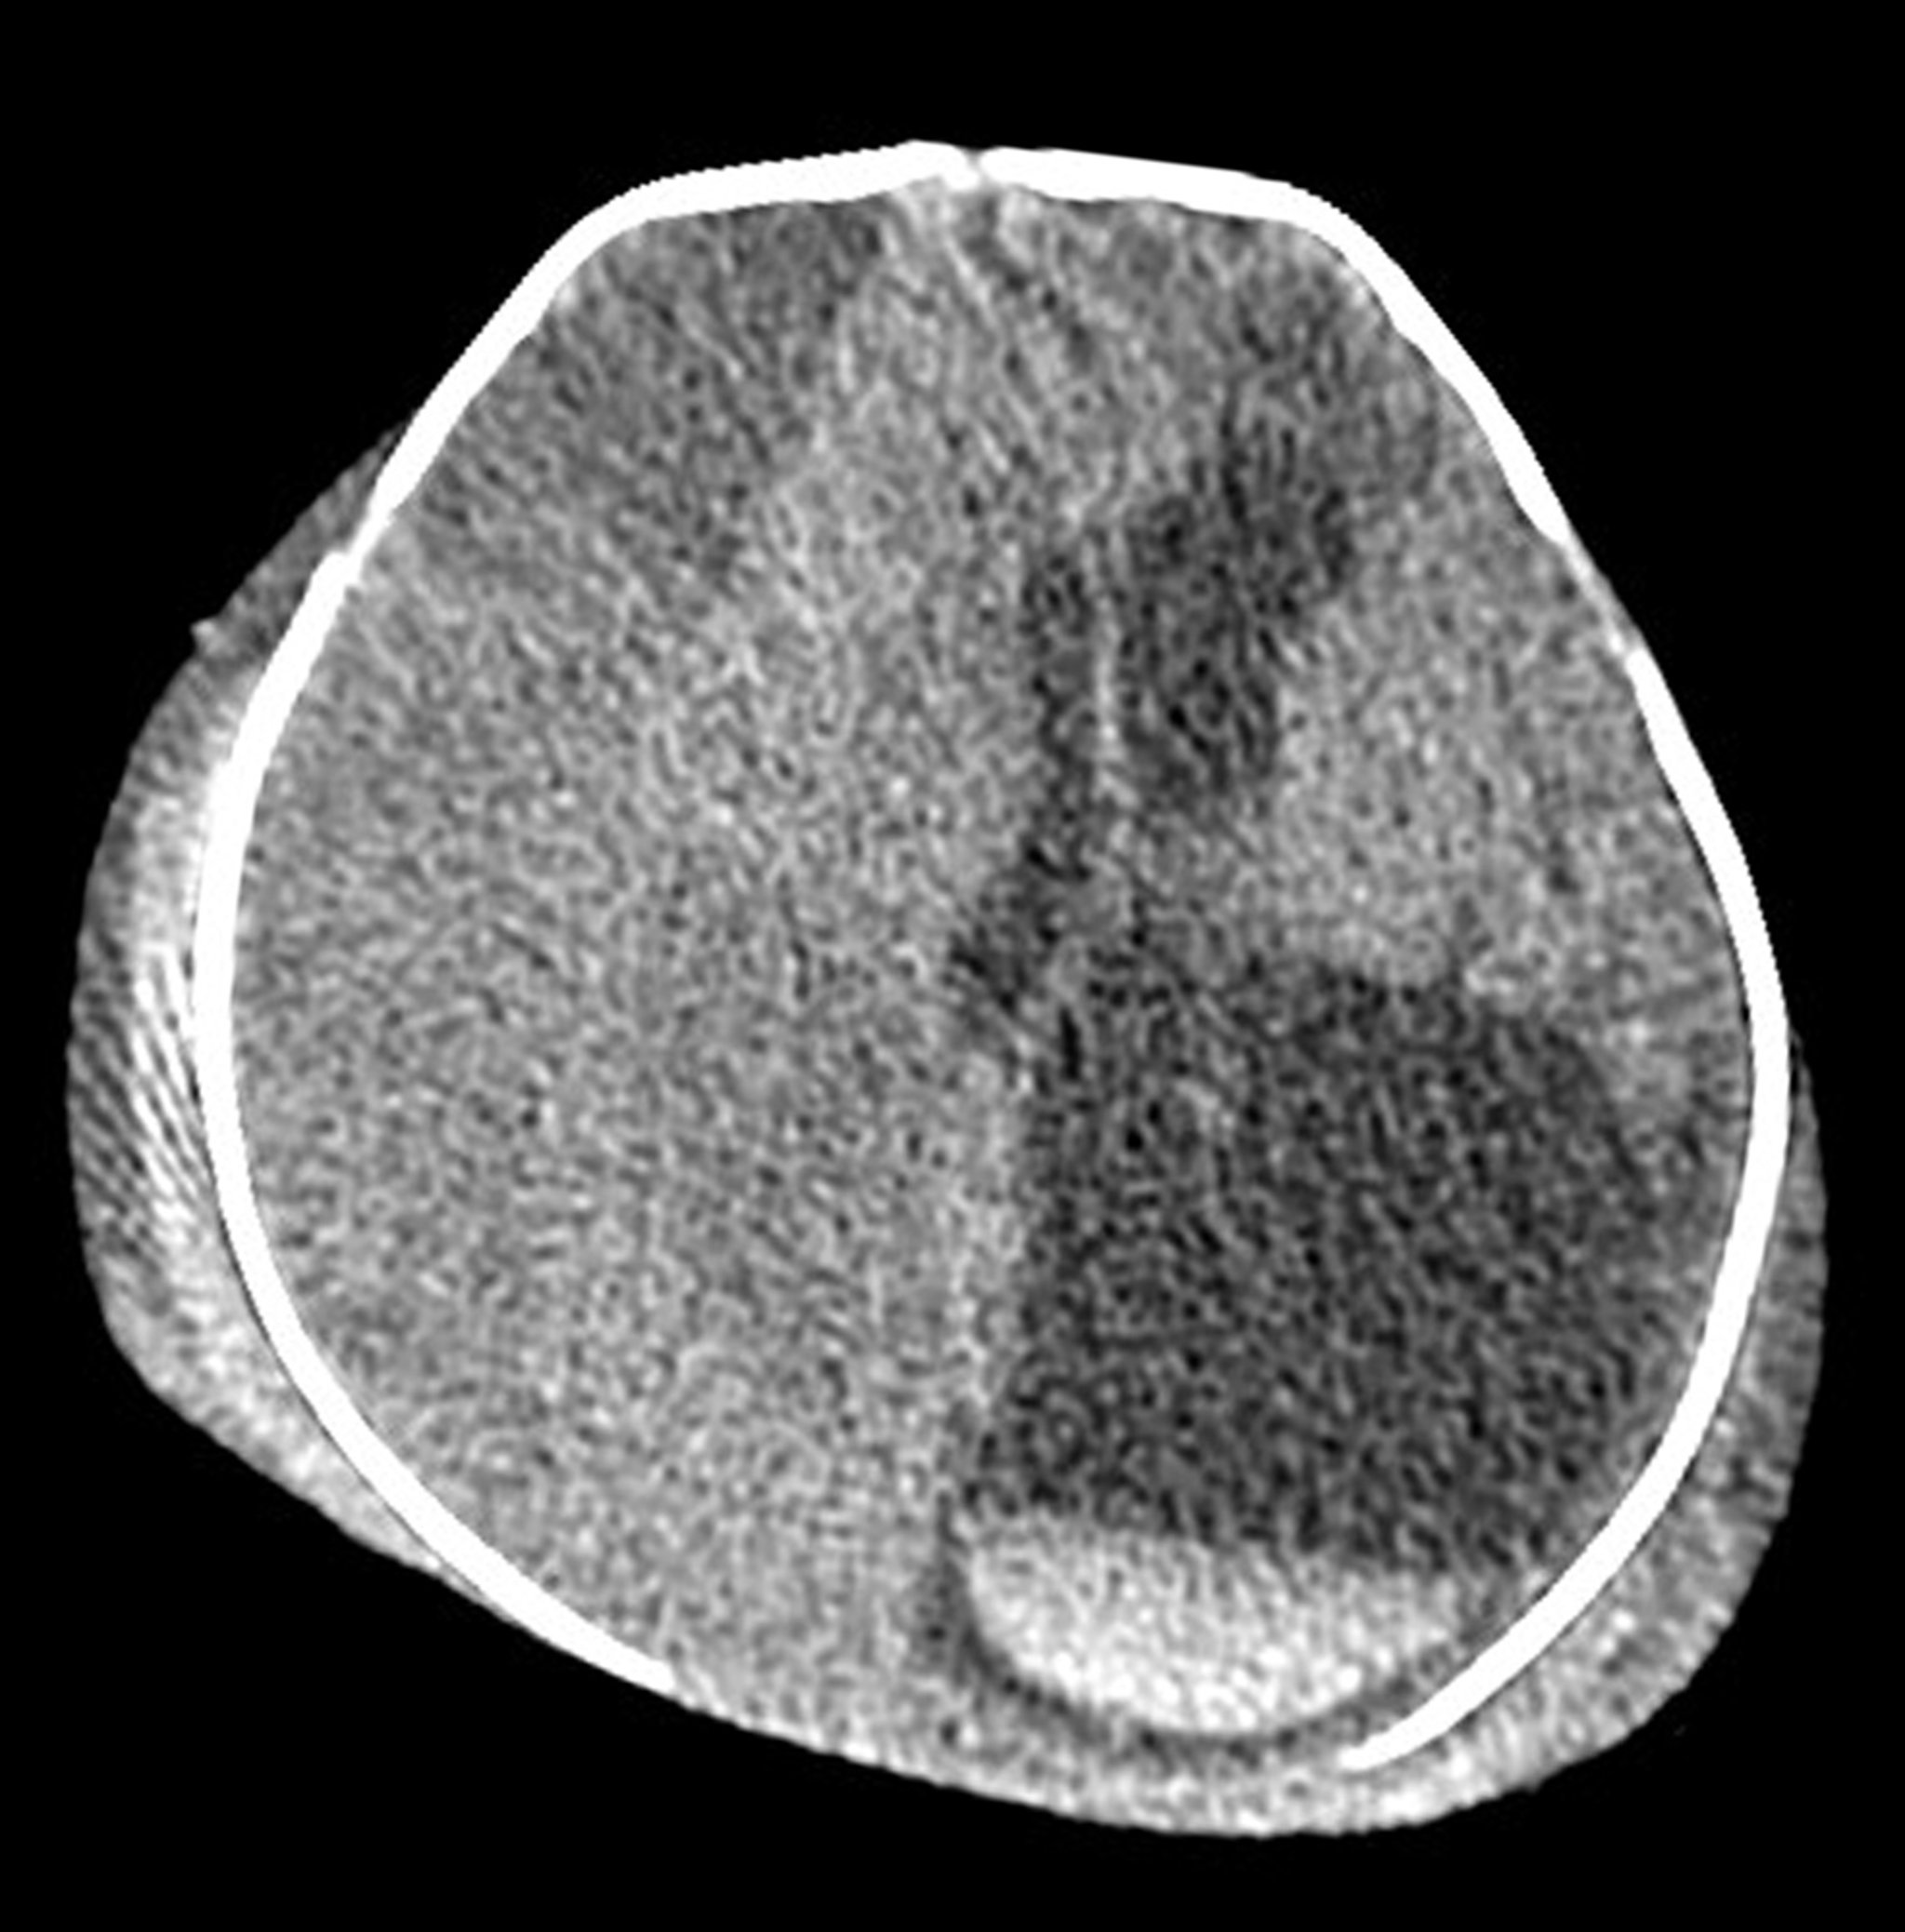

Lesiones extensas en un recién nacido (TC) relacionadas con el nacimiento

Esta TC axial (transversal) de la cabeza de un recién nacido muestra una lesión extracraneal e intracraneal extensa secundaria a una lesión grave relacionada con el nacimiento. Se observa edema bilateral/hematoma en el cuero cabelludo. Hay un hematoma subdural isodenso (subagudo) muy grande a lo largo del hemisferio cerebral derecho, que causa herniación cerebral a través de la línea media. El hematoma produce agrandamiento del ventrículo lateral izquierdo. En la parte inferior derecha de la imagen se observa una formación aguda en capas de sangre acumulada en la parte inferior del ventrículo lateral izquierdo (material blanco con una línea recta).